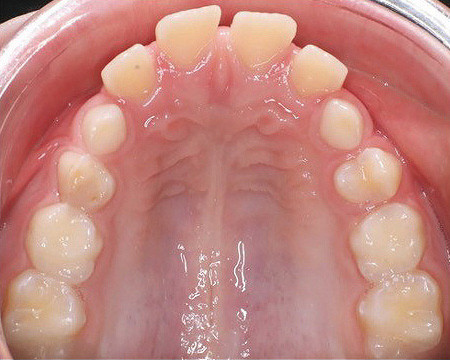

Klinisches Fallbeispiel 2 (Abb. 2a–y)

Distalbiss und tiefer Biss bei einem zwölfjährigen Mädchen. Die Behandlung erfolgte mit Invisalign und Precision Wings. Insgesamt waren zwei Schienensätze notwendig. Die Gesamtbehandlung dauerte 18 Monate.Bei der Planung des ClinCheck wurde der tiefe Biss vorwiegend über eine Intrusion der Unterkieferfront behoben, um die Lachlinie der Patientin nicht negativ zu beeinflussen. Die Oberkieferfront wurde nur retrudiert, jedoch vertikal nicht intrudiert. Während der Phase des Mandibular Advancement wurde die Wirkung der Precision Wings durch den Einsatz von Klasse II-Gummizügen unterstützt. Schlussendlich wurde auch der hängenden Okklusionsebene durch eine einseitige Intrusion der Molaren im ersten Quadranten Rechnung getragen.